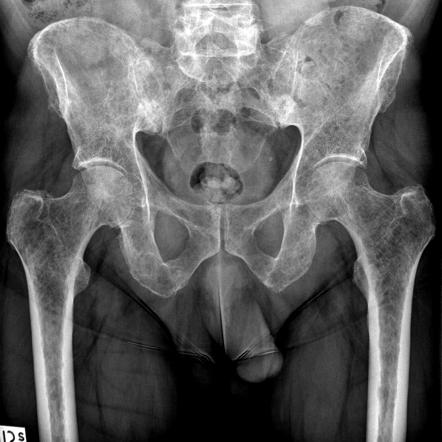

對疑似多發(fā)性骨髓瘤患者的診斷檢查通常包括骨骼檢查。

骨髓瘤活動有時表現(xiàn)為“溶解性病變”(由于再吸收導致正常骨的局部消失),并且在顱骨X射線上表現(xiàn)為“穿孔病變”(胡椒罐頭骨)。病變也可能是硬化的,被視為放射狀??偟膩碚f,骨髓瘤的放射密度在-30和120Hunsfield單位(HU)之間。

磁共振成像(MRI)在檢測裂解性病變方面比單純X射線更敏感,并且可能取代骨骼調查,特別是在懷疑椎病時。偶爾進行CT掃描以測量軟組織漿細胞瘤的大小。骨掃描通常在骨髓瘤患者的檢查中沒有任何額外的價值(沒有新的骨形成;在骨掃描中沒有很好地顯示溶解性病變)。